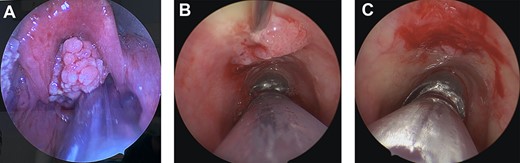

We planned to perform endoscopic sinus surgery with biopsy and excision of sinonasal tumour; however, on induction he was found to have a large supraglottic papillomatous lesion causing airway obstruction (Fig. 1A). Endoscopic assessment identified the extent of the sinonasal tumour, which involved the left anterolateral nasal wall, left septum (from Kiesselbach’s plexus to the posterior nasal septum) and then extended to the contralateral side through a perforation in the right mid septum and progressing to the anterior aspect of the right lateral nasal wall. The planned procedure was converted to a microlaryngoscopy with excision of supraglottic lesion, incisional biopsy of nasal papillomata and ligation of the left sphenopalatine artery (due to persistent bleeding). Tracheoscopy also identified a region of tracheal papilloma, which planned for surgical management later. Patient was extubated successfully and transferred to the High Dependency Unit for airway monitoring.

Intraoperative images. (A) Large, supraglottic, papillomatous lesion extending to petiole—excised at first surgery. (B) Tracheal papilloma being injected with Cidofovir at the base of lesion during second procedure. (C) Tracheal papilloma post debridement and injection of Cidofovir during the second procedure.

Two weeks later, he underwent a repeat microlaryngoscopy, tracheoscopy and debridement of tracheal papillomata with adjuvant cidofovir injection. The lesions treated were on the tracheal mucosa overlying the inferior aspect of the anterior cricoid and the left laryngeal ventricle (Fig. 1B and C). Four weeks later, an endoscopic septectomy, bilateral medial maxillectomy, right sphenoethmoidectomy and right sphenopalatine artery ligation were performed to eradicate sinonasal disease.